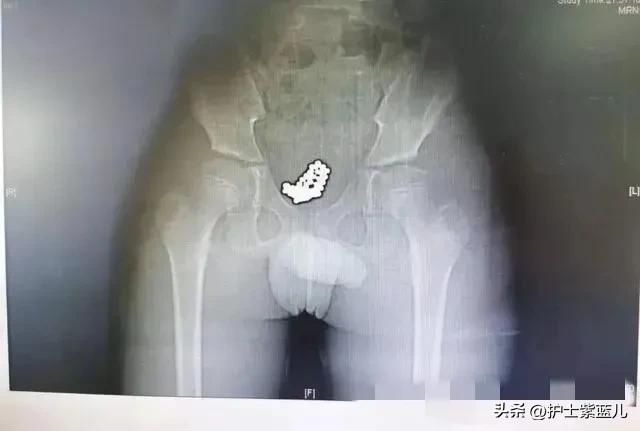

随后,医生建议拍了CT,拿到片子就医生就知道了怎么回事了。从片子可以清晰看到,男孩的膀胱里充满了一颗颗小珠子,直径大约5毫米 。

爸爸妈妈看到片子后,吓坏了!再次追问孩子,孩子才说,前一天晚上洗澡时出于好奇,将磁力珠从尿道口塞入尿道,没想到珠子进去就出不来了。

孩子想利用磁力珠的吸力将尿道内的珠子吸出,还把磁力珠吸成一长串以此来增大吸力。结果珠子进入容易出来难,导致越塞越多,一个也出不来!

最后,孩子住院接受膀胱异物取出手术。手术过程中,医生经尿道将输尿管镜推送至膀胱内,镜下见吸附到一起的磁珠体,磁珠之间吸附力强大,镜下无法一一分开,只能行膀胱切开异物取出术。术中将吸附在一起的磁珠体完整取出体外,经过检查,共计74颗。